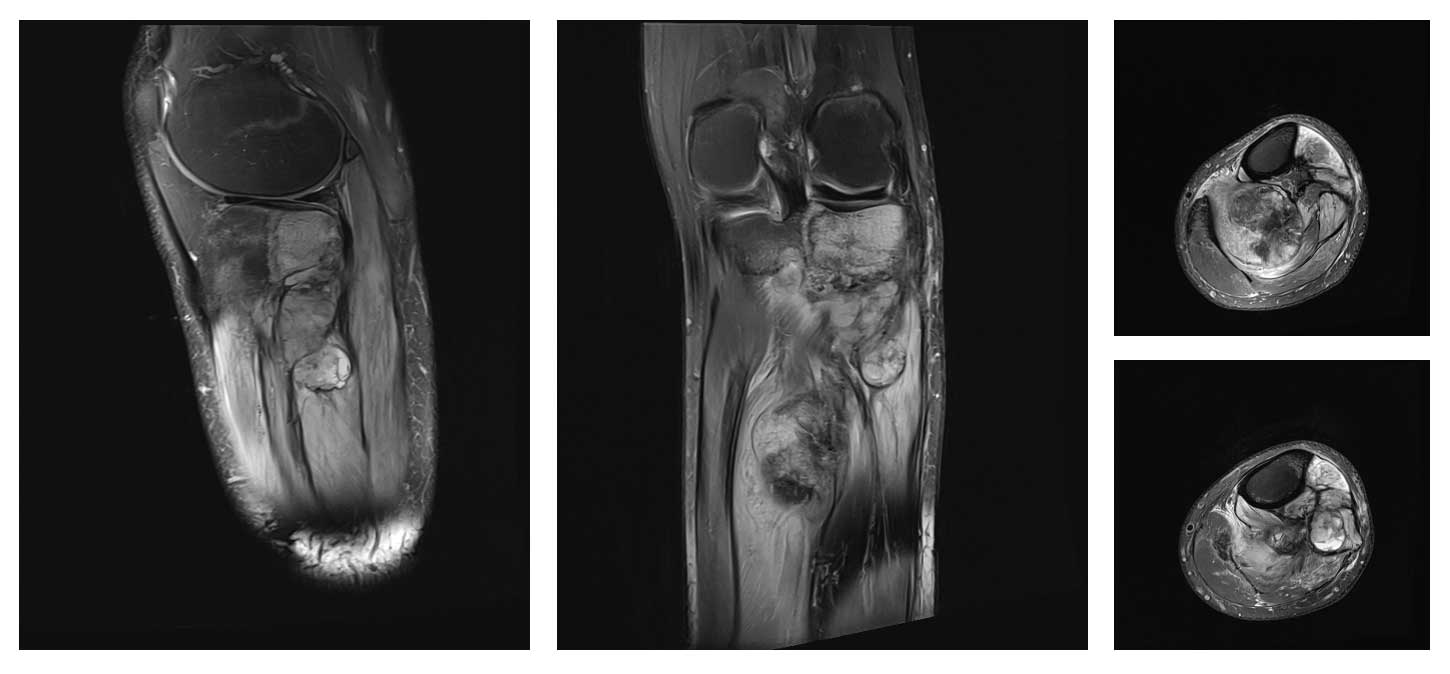

Ameliyat Öncesi: MR’da proksimal tibiada ve damar sinir paketini invaze eden düzensiz sınırlı yaygın tümör dokusu görülmekte.